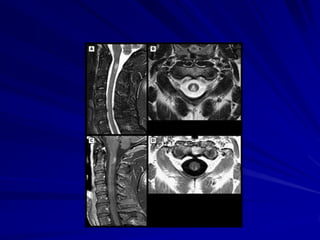

Diagnosis

MRI